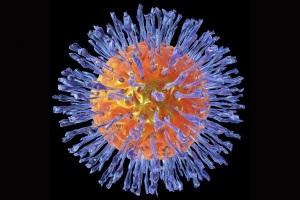

Кондиломи – це доброякісні аногенітальні бородавки, викликані вірусом папіломи людини, причому генотипи 6 і 11 вірусу виявляються більш ніж у 90% випадків.

Генітальний герпес може викликатися вірусами ВПГ-1 чи ВПГ-2. Герпетична інфекція виявляється або симптоматичним (клінічно вираженим) захворюванням на місці проникнення вірусу (тобто навколо геніталій), або протікає як безсимптомне захворювання.